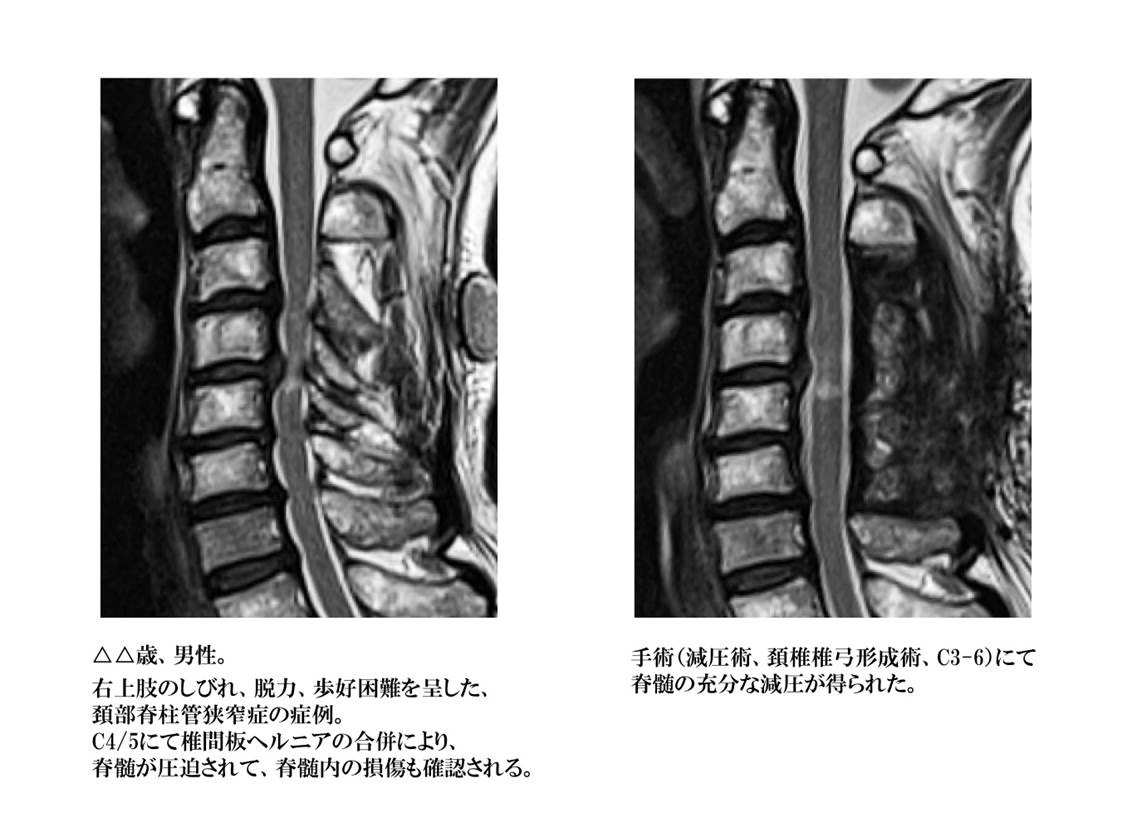

背骨の内部にある脊髄が通る部分を脊柱管と呼びます。長期間に及ぶ頚部、腰部への負担により椎体などの骨が変形したり、後方の椎弓と呼ばれる骨の間に存在している靱帯(黄色靱帯)が厚くなったりする(肥厚)ことにより、脊柱管が狭くなり、脊髄が圧迫されている状態です。脊髄周囲の隙間(くも膜下腔と言います)が狭くなり、脊髄が背骨の内部で窮屈な状態が続くと血液の通いも悪くなり、脊髄自体の働きが低下してくる可能性があります。

頚椎に発生した場合には上肢、手のしびれ感、感覚低下、疼痛、筋力低下、握力低下などの症状が一般的ですが、病状が進行していくと歩きづらくなったり、歩行中に膝の力が抜けて転びそうになると言った歩行困難なども出現してきます。症状か軽度であるうちは投薬、安静(外固定を含め)などにて症状の改善を認める場合がありますが、症状の悪化を認めたり、症状の出現から長期間が経過した場合には外科治療が必要になる場合があります。

また、狭窄症の程度が重く、脊髄が強く圧迫されている場合には、頭をぶつけたりの軽微な外力や転倒などの衝撃を受けた直後から手足がしびれて感覚がなくなり、物が持てなくなったり立ち上がれなくなったりする脊髄損傷としての症状が出現する場合があります。脊髄損傷による症状は、なかなか改善しづらいので後遺症として症状が残存する場合も多いので、その前に発見して治療を受けておかなければ行けない場合もあるので油断は禁物です。

減圧術

脊髄、神経は周囲を骨組織、靱帯、椎間板などにて囲まれているので、圧迫の原因となるのも周囲にある組織です。圧迫の場所、方向、程度などにて、手術の方法が決定されます。通常は前方及び後方から皮膚を切開して、脊椎周囲の筋肉の隙間を分け入り、必要最小限の骨組織を削除した後に、脊髄・神経を包んでいる硬膜を圧迫している原因病変を削除、摘出します。

椎間板ヘルニア、変形性頚椎症、脊柱管狭窄症、靱帯骨化症、アーノルド・キアリ奇形(I型)、末梢神経絞扼性疾患など、適応となる疾患は非常に多く、脊椎・脊髄疾患に対する外科治療の中で最も良く行われる手術法です。近年は如何に小さな皮膚の切開で治療を行うか、如何に脊椎周囲の筋肉の剥離を最小限に止めるか、如何に骨の削除範囲を少なくするかを考え、低侵襲での外科治療法が発達してきています。